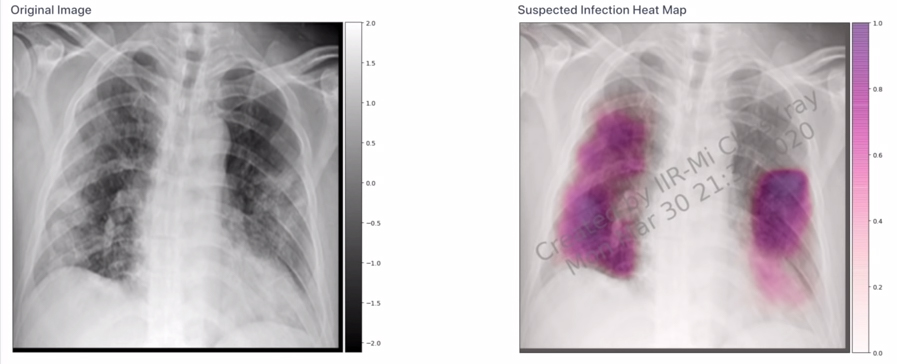

▼成大五人團隊研發出以AI人工智慧判讀肺部X光片,原本需要人工「40分鐘」判讀的過程,AI只消「1秒」就能判讀是否具有新冠特徵,讓醫師能更快下醫療決策。蔣榮先開心表示:「在網站上看見國旗,真是太令人興奮了」,並強調「MedCheX」系統檢測準確率高達92%,對此團隊決定「全球免費使用」。團隊參加的是競爭很大的「醫療科技類」,能獲選是莫大的成就。